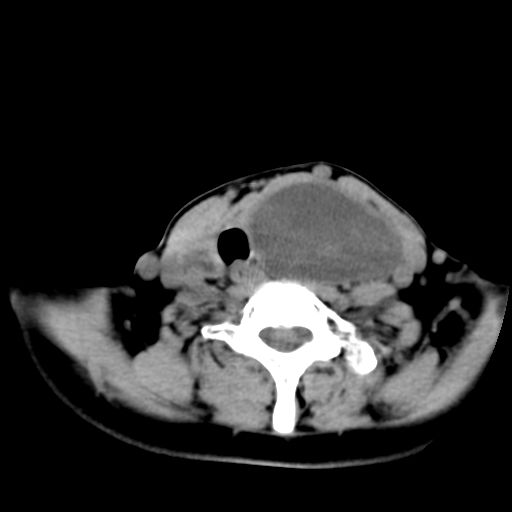

女  53岁  左侧甲状腺肿物3年,近2月明显增大。病理稍后发。

病灶虽未突破正常甲状腺组织,但边缘欠规整,且有近期明显增大史,考虑:甲状腺瘤恶变。

左侧甲状腺内见有一类圆形低密度区,边缘清楚光整,可见明显增强,间隔亦可见增强,且与周围组织分解清晰,周围组织间隙内未见肿大淋巴结。右侧亦可见类似表现。考虑甲状腺腺瘤。

手术病理证实:双侧腺瘤样甲状腺肿。